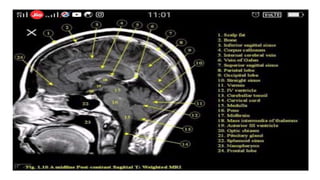

Sagittal T1 (Normal)

T1

• Provides the most anatomically-relevant images

• Fluid (in CSF and orbits) is dark

• Grey matter is darker than the white matter